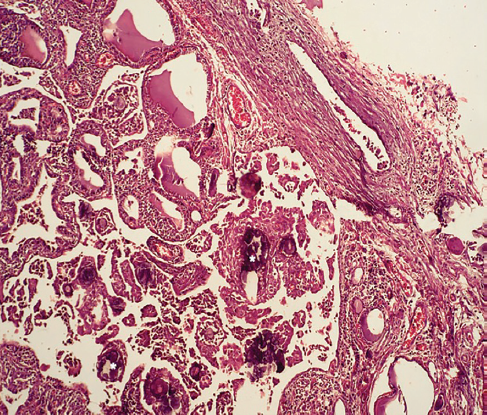

El reporte final de patología reveló formación difusa de folículos y papilas con cambios nucleares y abundantes cuerpos de psammoma en ambos lóbulos sin una cápsula identificable (figura 5), además de un nódulo de 5 mm en el lóbulo izquierdo con las mismas características, pero con formación de cápsula (figura 6).

Figura 5 Parénquima tiroideo con formación de folículos y papilas con cambios nucleares de CPT y abundantes cuerpos de psammoma (*).

Foto: Otorgada por los autores